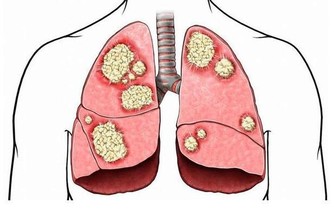

莫名的過敏,包括氣喘、慢性咳嗽、過敏性鼻炎